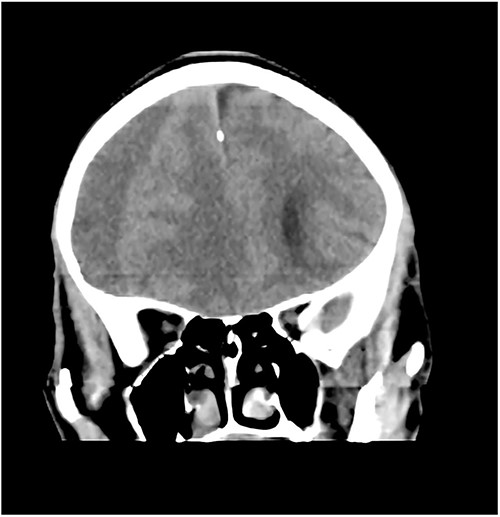

Case 4 – spontaneous CSDH in a young fit adult following ‘Bumpy Rides’

A 40-year-old military man who presented with a 1-week history of severe generalized headaches that was unresponsive to analgesics. He had two episodes of non-projectile vomiting before presentation. There were no other symptoms. He denied any history of trauma. He was not on any anticoagulants and had been otherwise healthy. Neurologic exam was normal. Brain CT scan done showed a right-sided fronto-parietal CSDH (Fig. 5). With this finding, he was further questioned about his daily routines/activities. It was at this point that he admitted to being part of an oil pipeline surveillance team in the Niger Delta region of Nigeria. He recounted that his job involved riding in an open van on very bumpy roads. And so, given the absence of any trauma, we hypothesized that this ‘roller coastertype phenomenon may be responsible for his CSDH. He underwent burr hole drainage and had complete resolution of his symptoms in 48 hours and was discharged home on the 3rd day post op.